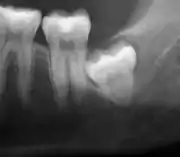

Impacted wisdom teeth are classified by their direction of impaction, their depth compared to the biting surface of adjacent teeth and the amount of the tooth's crown that extends through gum tissue or bone. Impacted wisdom teeth can also be classified by the presence or absence of symptoms and disease. Screening for the presence of wisdom teeth often begins in late adolescence when a partially developed tooth may become impacted. Screening commonly includes a clinical examination as well as x-rays such as panoramic radiographs.

If the tooth cannot be assessed with clinical exam alone, the diagnosis is made using either a panoramic radiograph or cone-beam CT. Where unerupted wisdom teeth still have eruption potential several predictors are used to determine the chance of the teeth becoming impacted. The ratio of space between the tooth crown length and the amount of space available, the angle of the teeth compared to the other teeth are the two most commonly used predictors, with the space ratio being the most accurate. Despite the capacity for movement into early adulthood, the likelihood that the tooth will become impacted can be predicted when the ratio of space available to the length of the crown of the tooth is under 1.[5]: 141